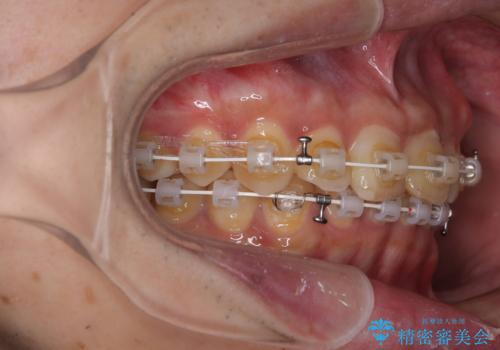

- 審美装置

補助装置を用いて、上顎大臼歯を積極的に後方移動させながら、ディープバイトを改善していくこととしました。

強い咬合力に抵抗するため、上下ともに表側のワイヤー装置にて矯正治療を行うこととしました。